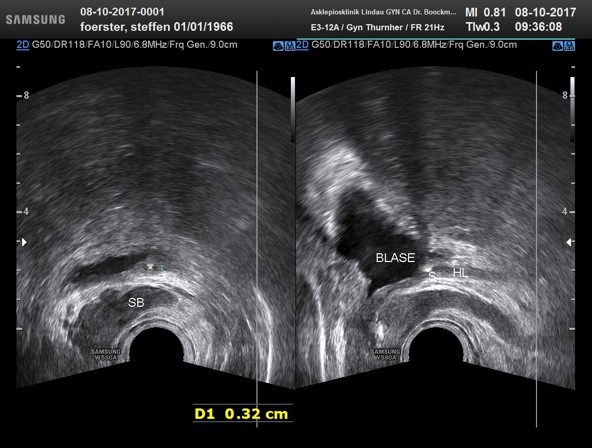

Bedeutung der Retroperitonealesonographie beim Harnleiterstein mit Harnstauungsniere